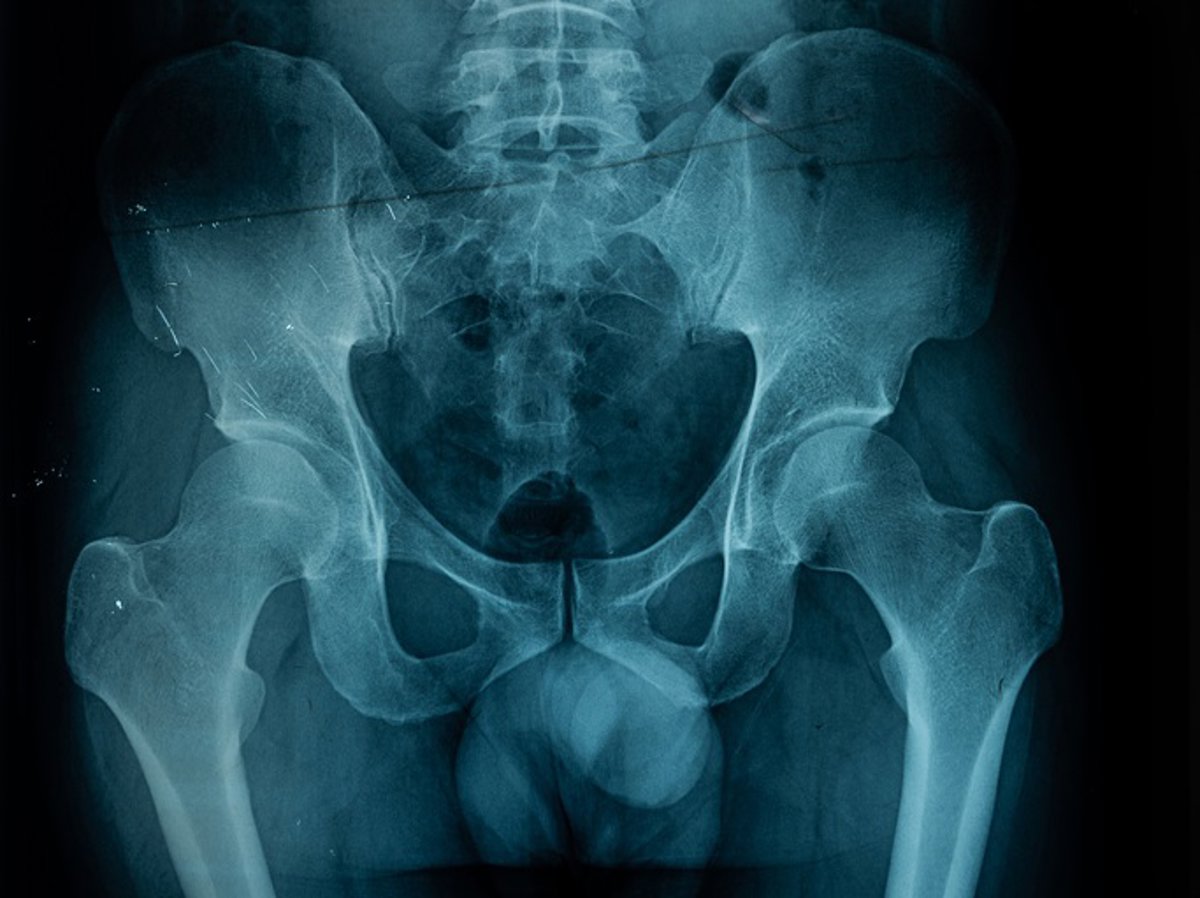

Archivo - Osteoporosis.

Archivo - Osteoporosis. - KOOL99/ ISTOCK - Archivo